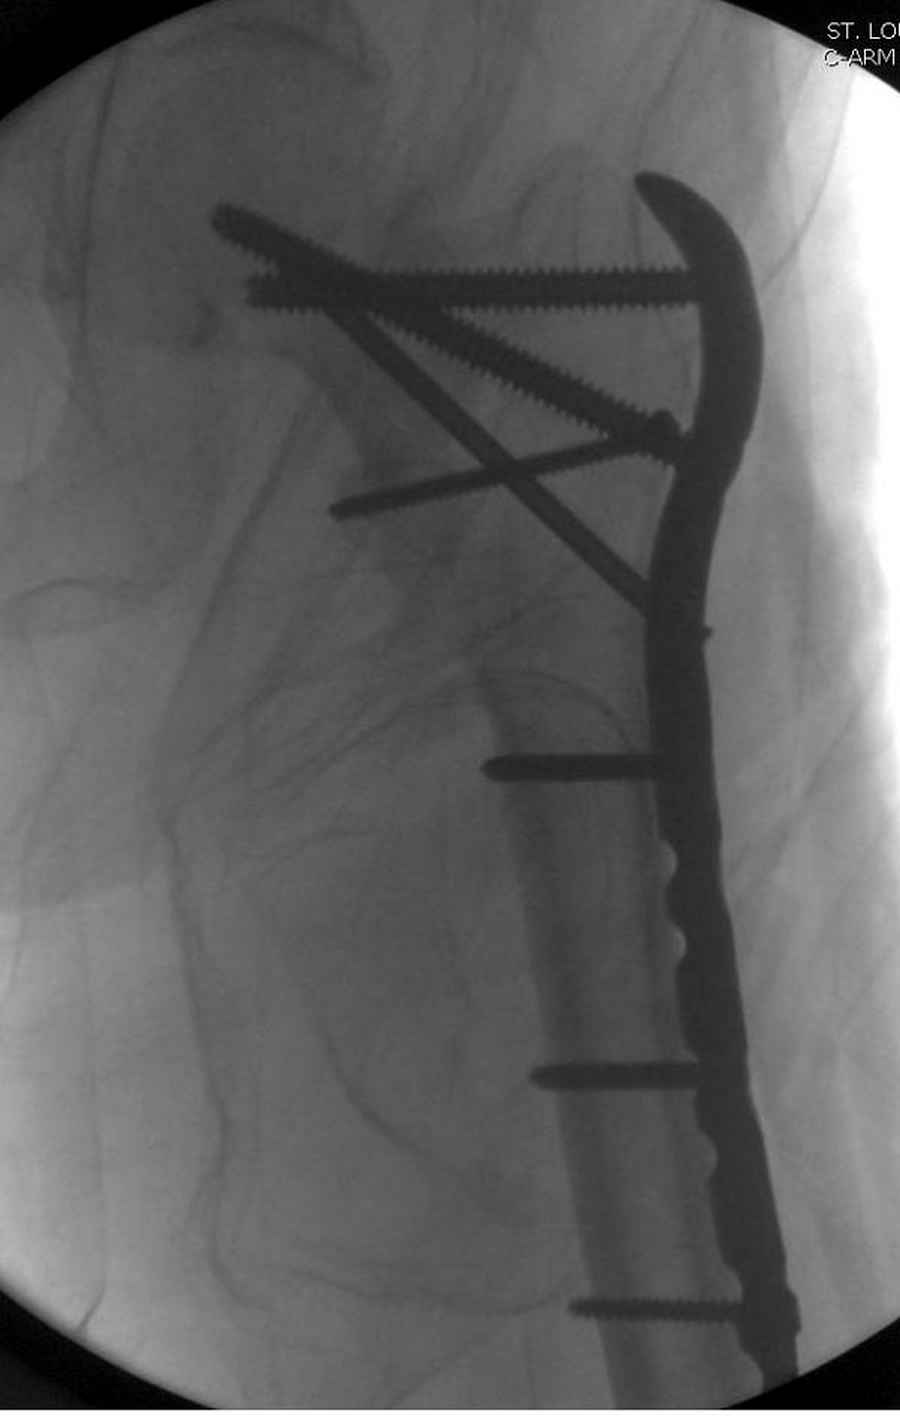

Здесь пара случаев фиксации похожих переломов:

первый высокоэнергетическая травма 36 лет

Djoldas Kuldjanov, M.D.

Department of Orthopedic Surgery

St. Louis University